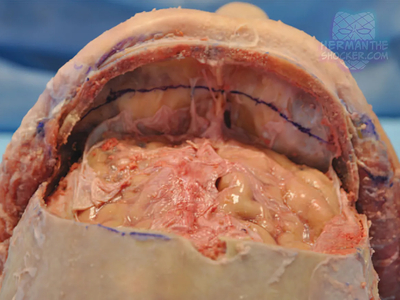

Composite facial allografts have become increasingly popular in the reconstruction of complex facial defects. Good to excellent aesthetic results can be achieved, particularly when a foundation of donor skeleton has been transferred...